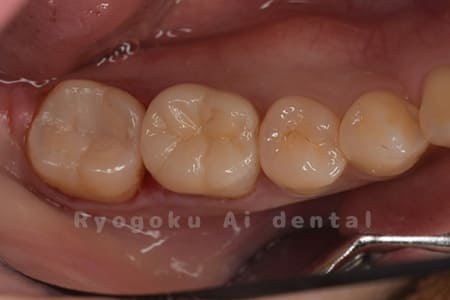

Case07

- セラミッククラウン

銀歯が浮いた感じがする、と相談された患者さんです。銀歯を外し、虫歯治療を行い、セラミックの被せ物で治療を行いました。